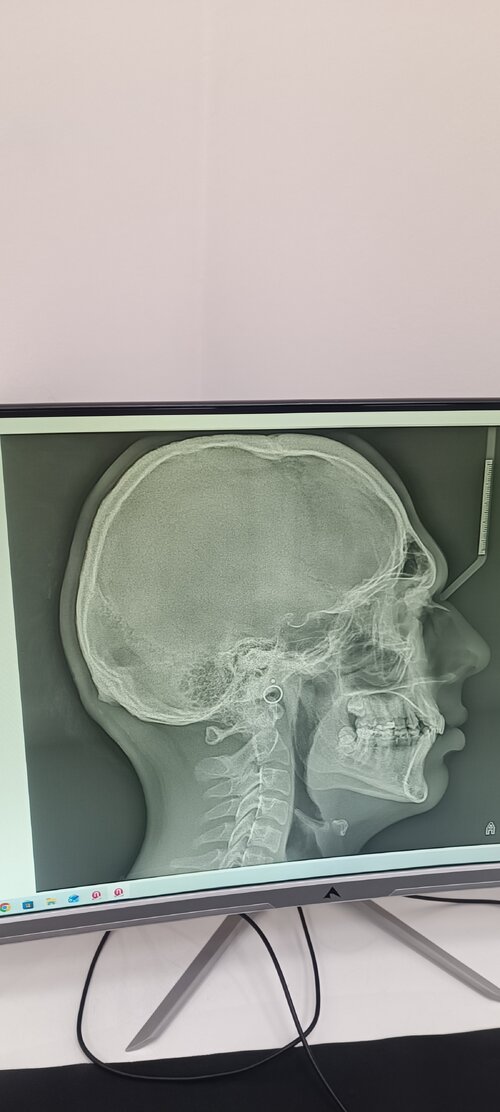

Kinda curious,is my maxilla recessed or flat?

• IMG_20260223_090633.jpg